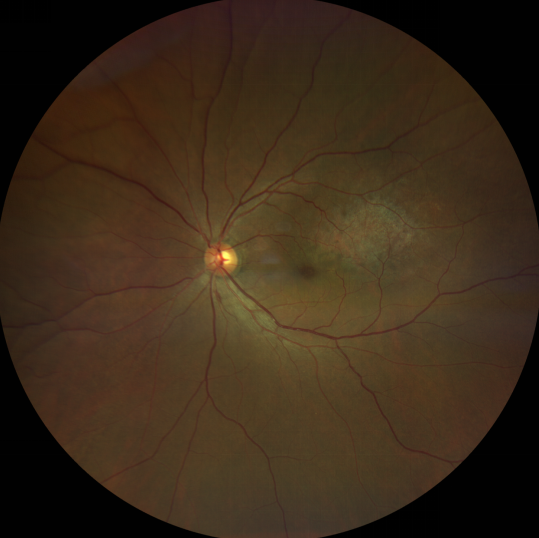

脈絡(luò)膜黑色素瘤是成年人常見的眼內(nèi)惡性腫瘤,其患病率在我國居眼內(nèi)惡性腫瘤的第二位,僅次于視網(wǎng)膜母細胞瘤。其惡性程度高,不僅可致患者喪失視力,而且嚴(yán)重威脅患者生命,即使在沒有明確轉(zhuǎn)移前摘除患眼眼球,其5年死亡率也有17%-53%。

脈絡(luò)膜黑色素瘤是葡萄膜惡性腫瘤中較多的一種。葡萄膜腫瘤主要發(fā)生于脈絡(luò)膜、睫狀體和虹膜。其中,脈絡(luò)膜腫瘤占80%,睫狀體腫瘤占12%,虹膜腫瘤占8%。惡性程度高的腫瘤主要發(fā)生于脈絡(luò)膜。發(fā)生于睫狀體的腫瘤惡性程度偏低,發(fā)生于虹膜的腫瘤多數(shù)為良性。脈絡(luò)膜黑色素瘤的特點是惡性程度高、易侵襲轉(zhuǎn)移、預(yù)后極差,嚴(yán)重威脅患者的視力和生命。其發(fā)病率有種族差異性,以高加索及白種人居多,黑人發(fā)病率低,亞洲人居于中間。

脈絡(luò)膜黑色素瘤患者在發(fā)病早期無眼痛等癥狀,當(dāng)腫瘤較小時較難發(fā)現(xiàn),隨著病程進展,腫瘤增大,發(fā)生滲出性視網(wǎng)膜脫離或累及黃斑,視力下降才就診。

脈絡(luò)膜黑色素瘤惡性程度高,50%的患者會發(fā)生轉(zhuǎn)移,轉(zhuǎn)移到肝、肺等遠處臟器,常見的轉(zhuǎn)移方式是經(jīng)鞏膜導(dǎo)管擴散,經(jīng)視神經(jīng)蔓延者罕見。一旦發(fā)生轉(zhuǎn)移,1年生存率只有10%,即絕大多數(shù)病人在半年至1年間會失去生命。因此,早期診斷和選擇合適的治療方式對有效提高局部腫瘤的控制率、降低腫瘤的遠處轉(zhuǎn)移率、延長患者的生存率具有重要意義。